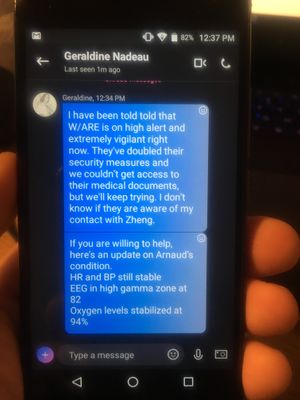

From: Geraldine Nadeau Thank you so much. I have been told that W/ARE is on high alert and extremely vigilant right now. They've doubled their security measures and we couldn't get access to their medical documents, but we'll keep trying. I don't know if they are aware of my contact with Zheng. If you are willing to help, here's an update on Arnaud's condition. HR and BP still stable EEG in high gamma zone at 82 Oxygen levels stabilized at 94%